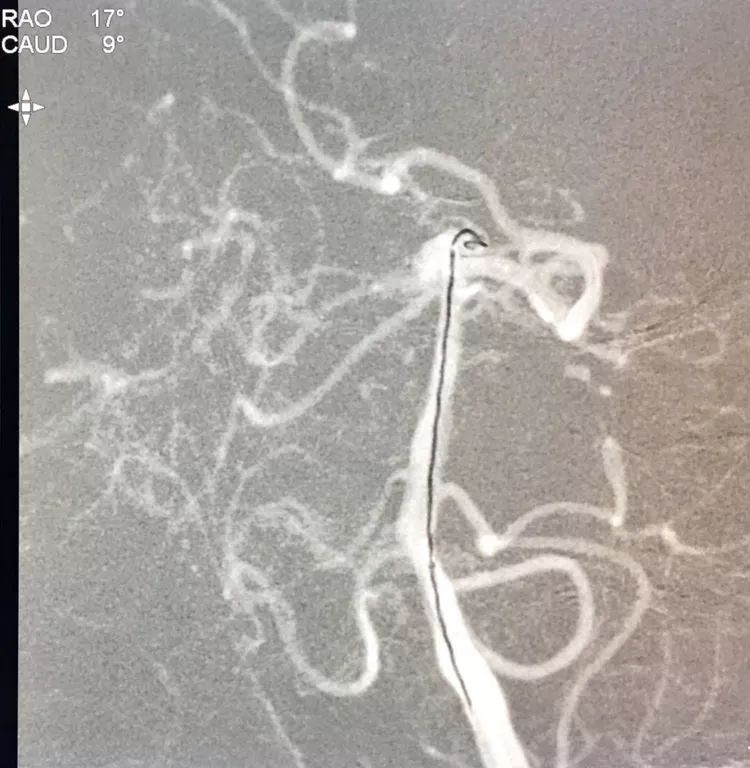

在支架保护下输送弹簧圈栓塞瘤腔

此时从工作位(右斜17°反汤9°)看弹簧圈分布致密,微导管头已被顶到瘤颈处

工作位造影看动脉瘤栓塞满意,子瘤已不显影,是不是可以收手了呢?